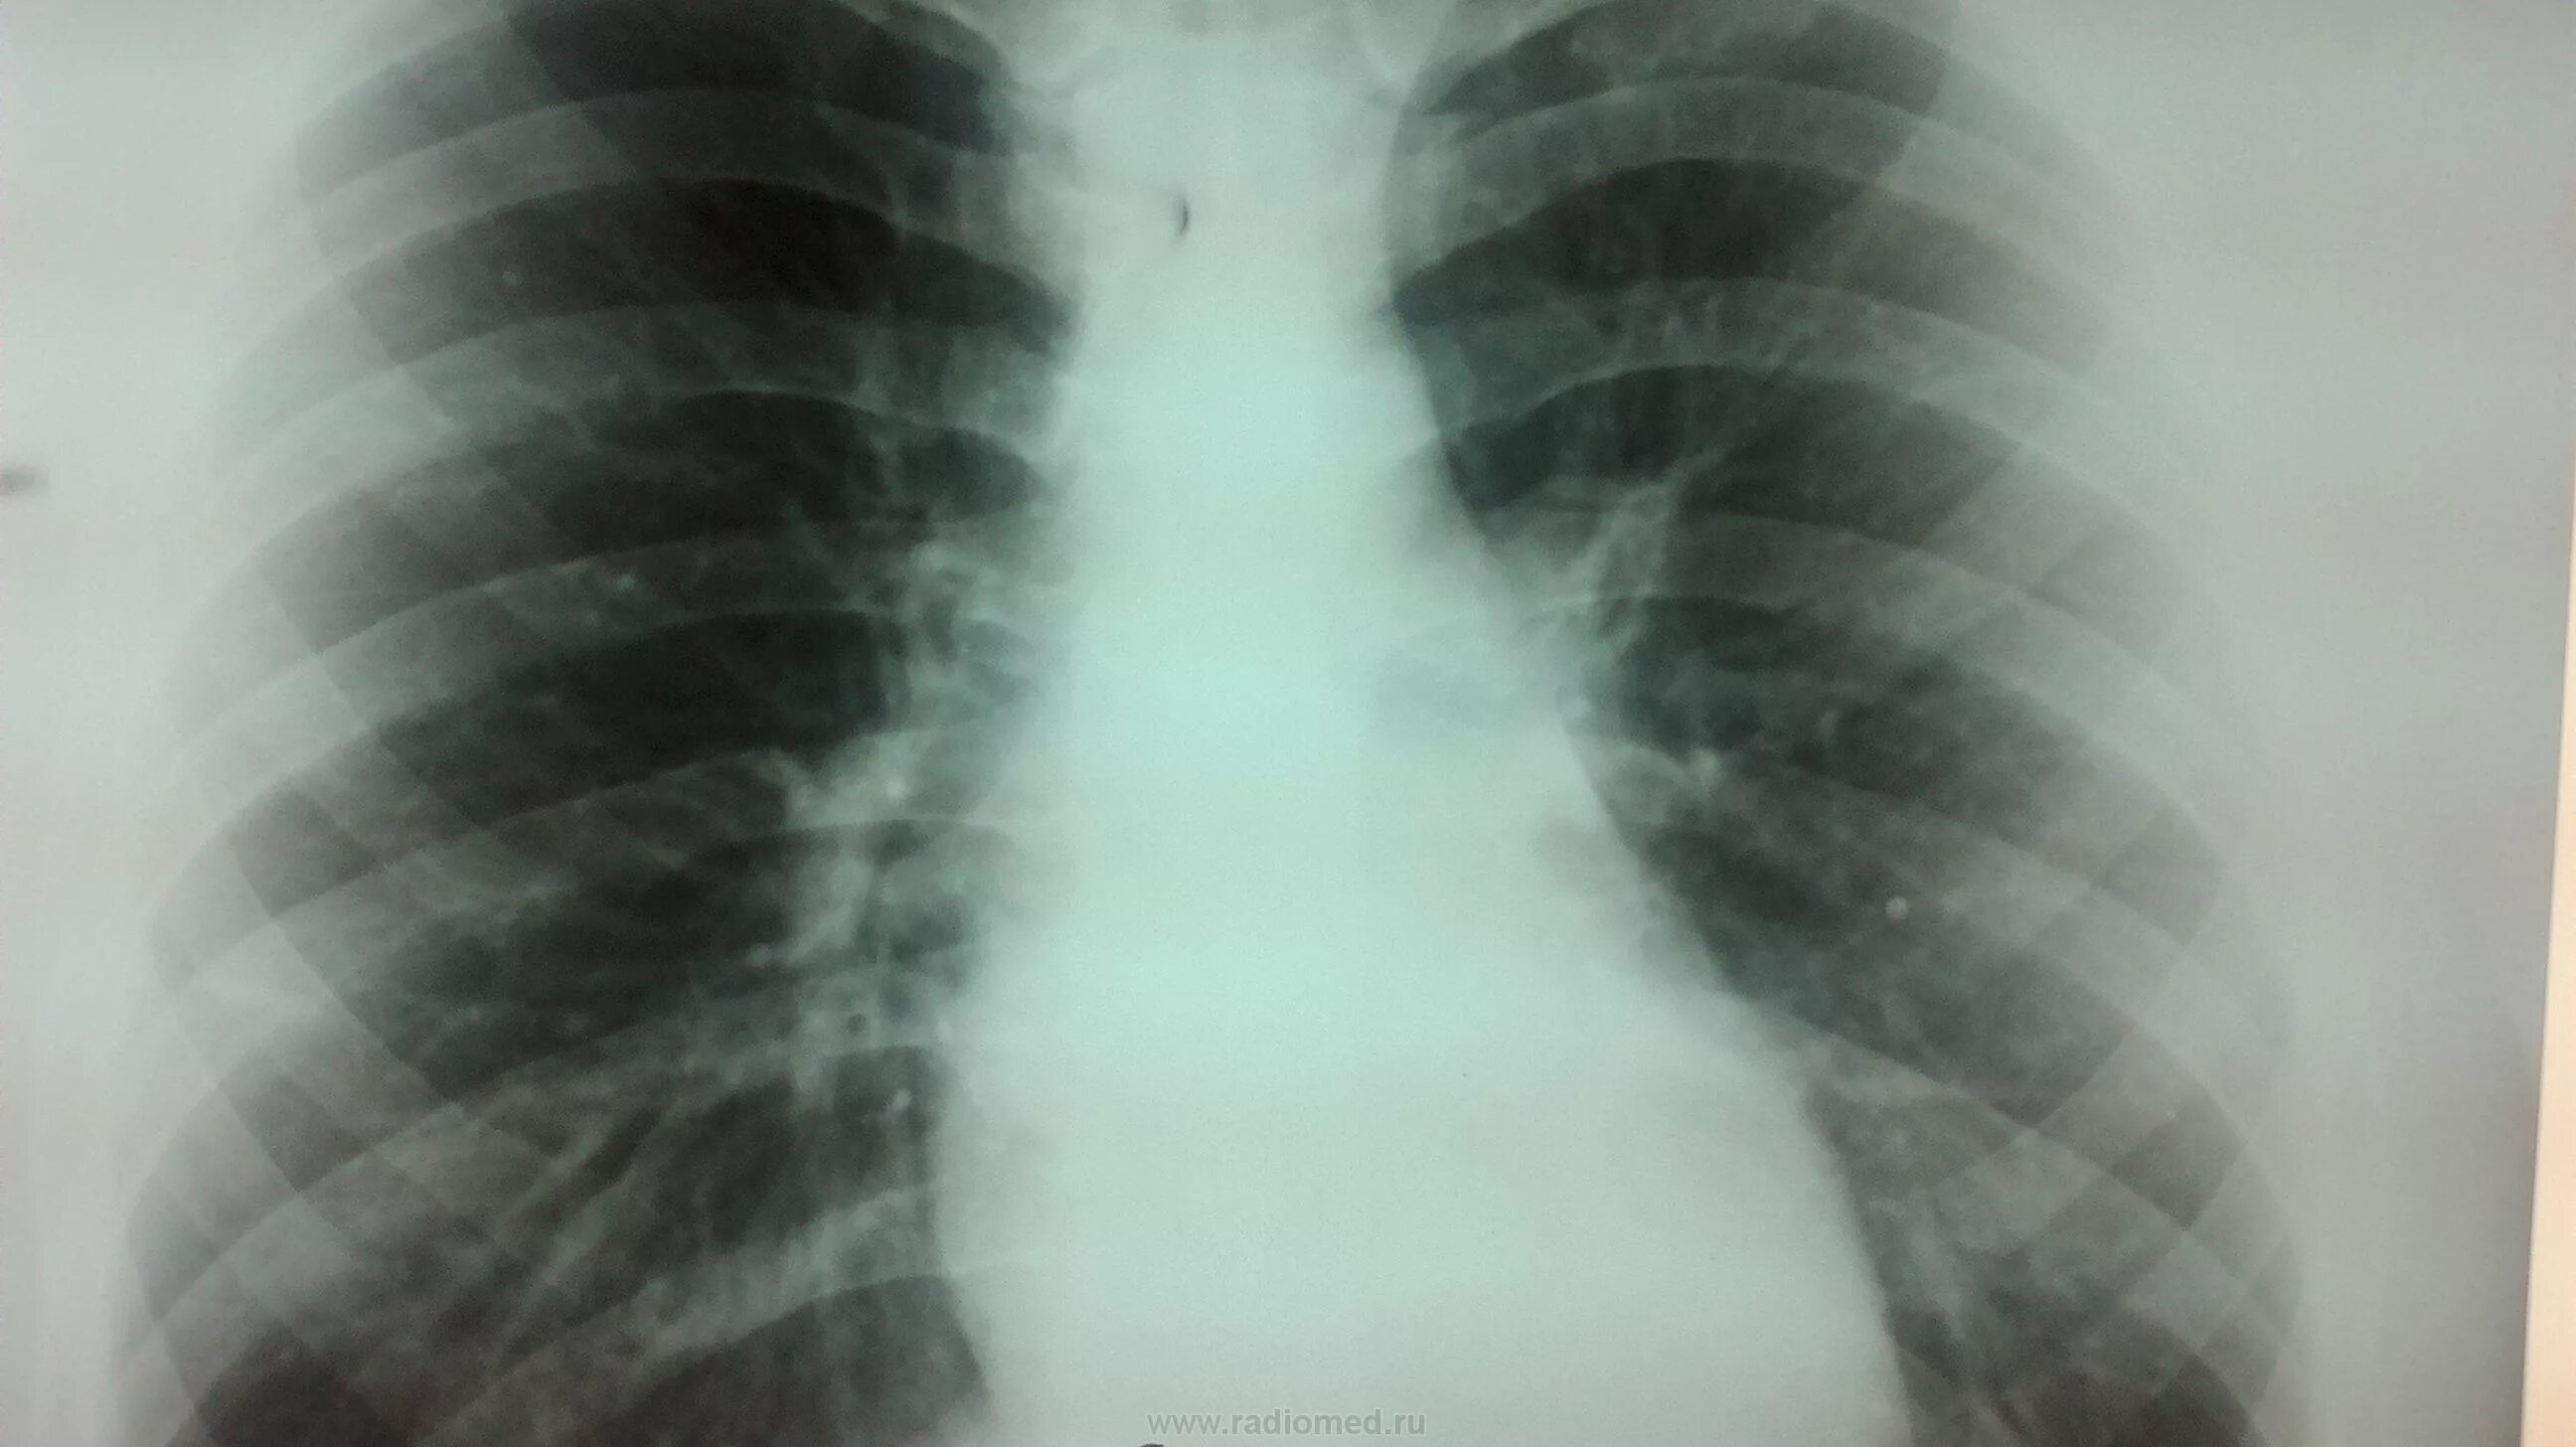

Диффузный эндобронхит